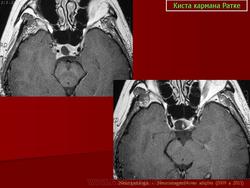

ГМ. Киста кармана Ратке. +

Киста кармана Ратке

Именно, формирующеес первичное, в кранем случае вторичное "пустое" турецкое седло. Уважаемый Валентин Львович, прошу прощения за поднятые здесь дебаты, это не неуважение к Вам или вашим источникам, а просто обмен мнениями по поводу спорного на наш взгляд наблюдения. Потом всё можно удалить. Интересно, какие будут мнения у других....